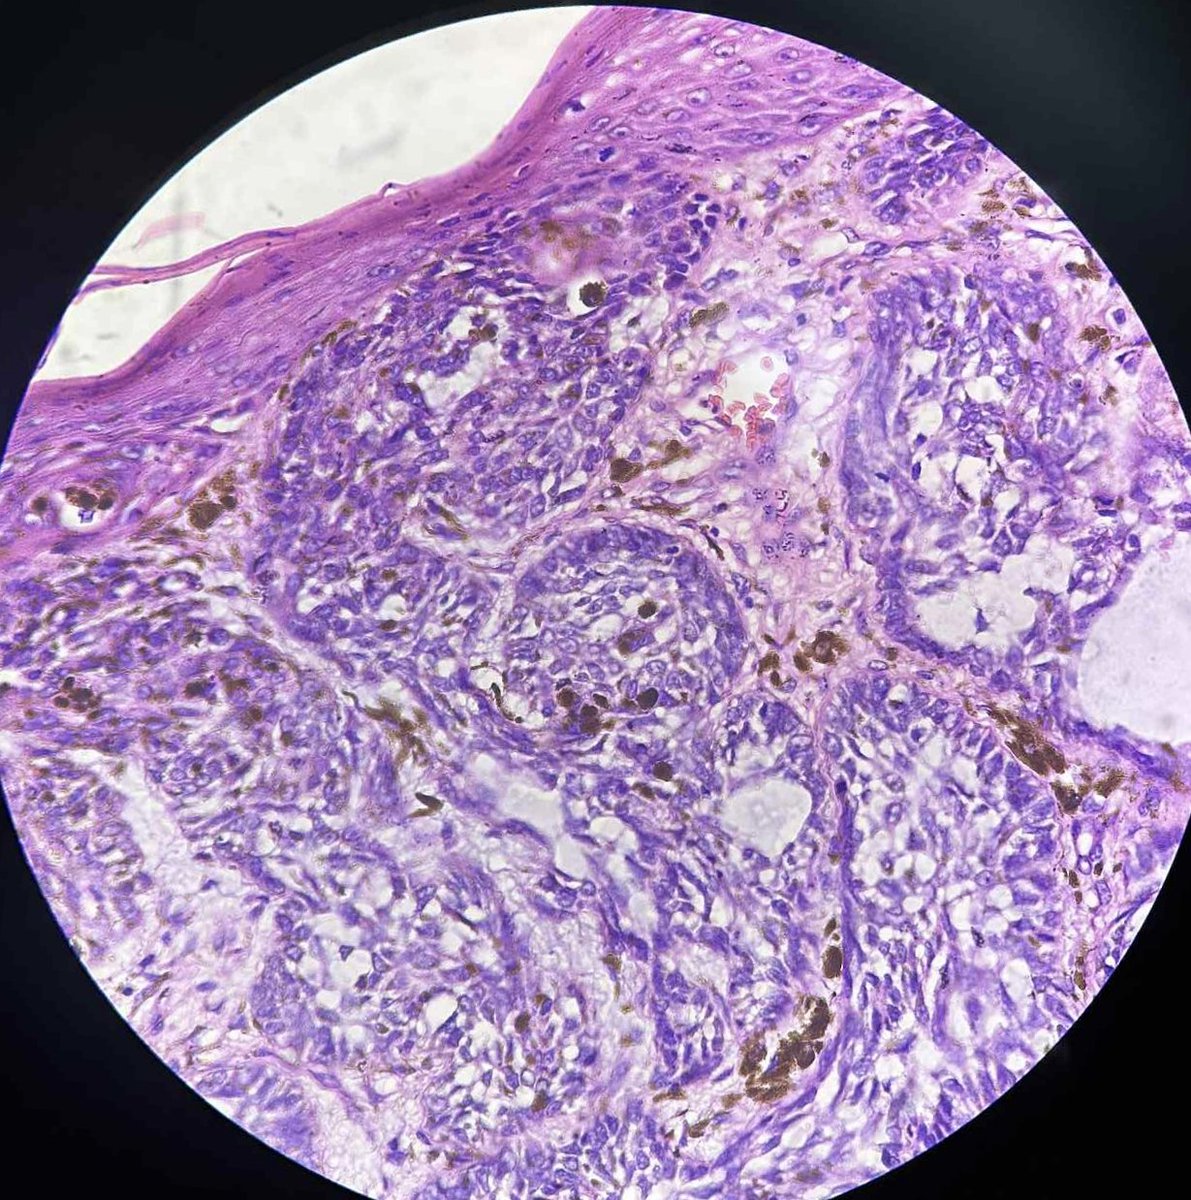

41 yrs old male with mole on head. A nice example of cystic pigmented basal cell carcinoma. #pathology #dermpath #BCC